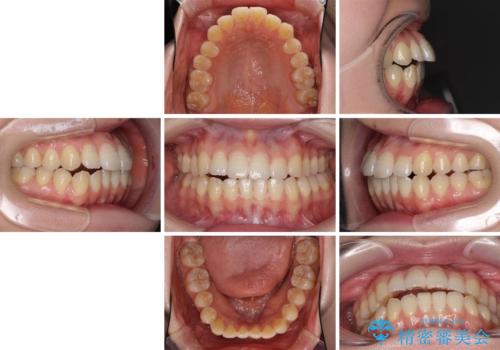

オープンバイトのインビザラインを用いた再矯正

- 矯正治療の後戻りを気にして来院された患者様です。

オープンバイト(前歯の開咬)と下顎骨の偏位による不正咬合が認められました。

骨格の偏位による不正咬合は改善しきれないことを理解いただいた上で、インビザラインにて矯正治療を行うこととしました。

オープンバイトは後戻りを起こしやすいため、極力そのリスクを軽減するため、奥歯を圧下させるように治療を進めていきました。

下顎骨の偏位が顕著であったため、上下の正中を合わせることはできませんでしたが、患者様には大変満足していただきました。